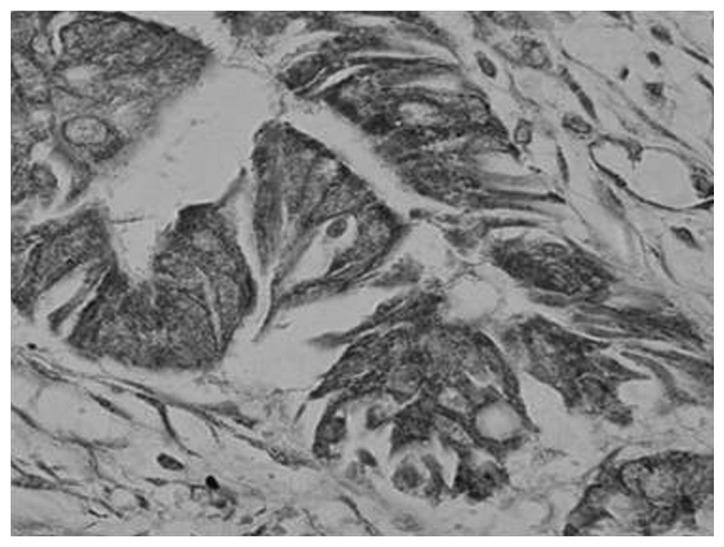

The present report investigated the correlation between the expression levels of matrix metalloproteinase (MMP)-9 in gastric carcinoma patients and the clinicopathological characteristics. Forty-five samples of gastric carcinoma and distal gastric mucosa tissue, and 10 samples of healthy gastric mucosa tissue were analyzed using semi-quantitative polymerase chain reaction, as well as immunohistochemical and hematoxylin and eosin staining. MMP-9 protein levels in serum samples from the same patients were quantified by enzyme-linked immunosorbent assay. The present report identified that MMP-9 expression was markedly higher in the gastric carcinoma tissue (86.67%) than in the adjacent healthy tissue (10.00%). A positive association was identified between the level of MMP-9 protein expression and the depth of cancer invasion (P<0.05). Furthermore, the preoperative serum levels of the MMP-9 protein in the gastric carcinoma tissue were correlated with the tumor-node-metastasis stage and occurrence of lymph node metastasis (P<0.01). Data from the present report indicates that MMP-9 may be key in gastric carcinoma malignancy, and implies that MMP-9 may serve as a novel biomarker in the diagnosis and prognosis of gastric carcinoma.

本报告研究了胃癌患者基质金属蛋白酶(MMP)-9表达水平与临床病理特征之间的相关性。采用半定量聚合酶链反应、免疫组织化学及苏木精-伊红染色法,对45份胃癌及远端胃黏膜组织样本和10份健康胃黏膜组织样本进行了分析。通过酶联免疫吸附测定法定量检测同一患者血清样本中MMP-9蛋白水平。本报告发现,MMP-9在胃癌组织中的表达(86.67%)明显高于相邻健康组织(10.00%)。MMP-9蛋白表达水平与癌症浸润深度呈正相关(P<0.05)。此外,胃癌组织中MMP-9蛋白的术前血清水平与肿瘤-淋巴结-转移分期及淋巴结转移的发生相关(P<0.01)。本报告的数据表明,MMP-9可能在胃癌恶性肿瘤中起关键作用,这意味着MMP-9可能作为胃癌诊断和预后的一种新型生物标志物。